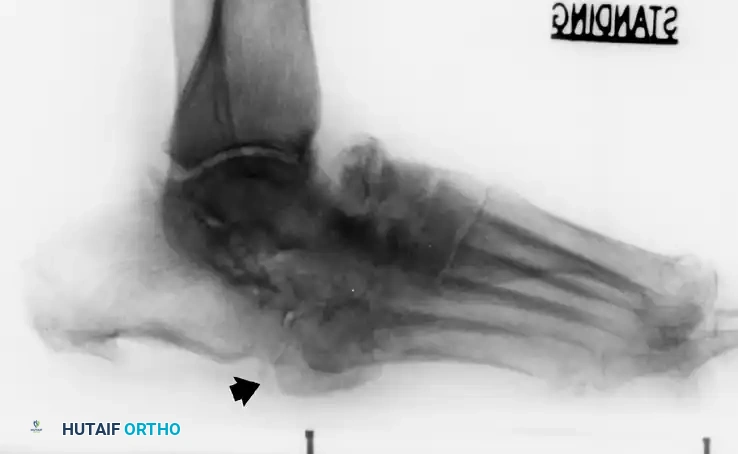

صورة تظهر قصر وانحراف العظام في القدم المصابة

في الحالات التي يصعب فيها التمييز بين اعتلال مفصل شاركو والتهاب العظم والنقي (العدوى العظمية)، قد يطلب الطبيب إجراء فحوصات متقدمة مثل التصوير بالرنين المغناطيسي أو المسح الذري للعظام باستخدام التكنيتيوم والإنديوم، والتي تساعد بشكل كبير في تأكيد وجود العدوى من عدمه.

أشعة سينية أمامية وجانبية تظهر تدمير المفاصل الرصغية المشطية